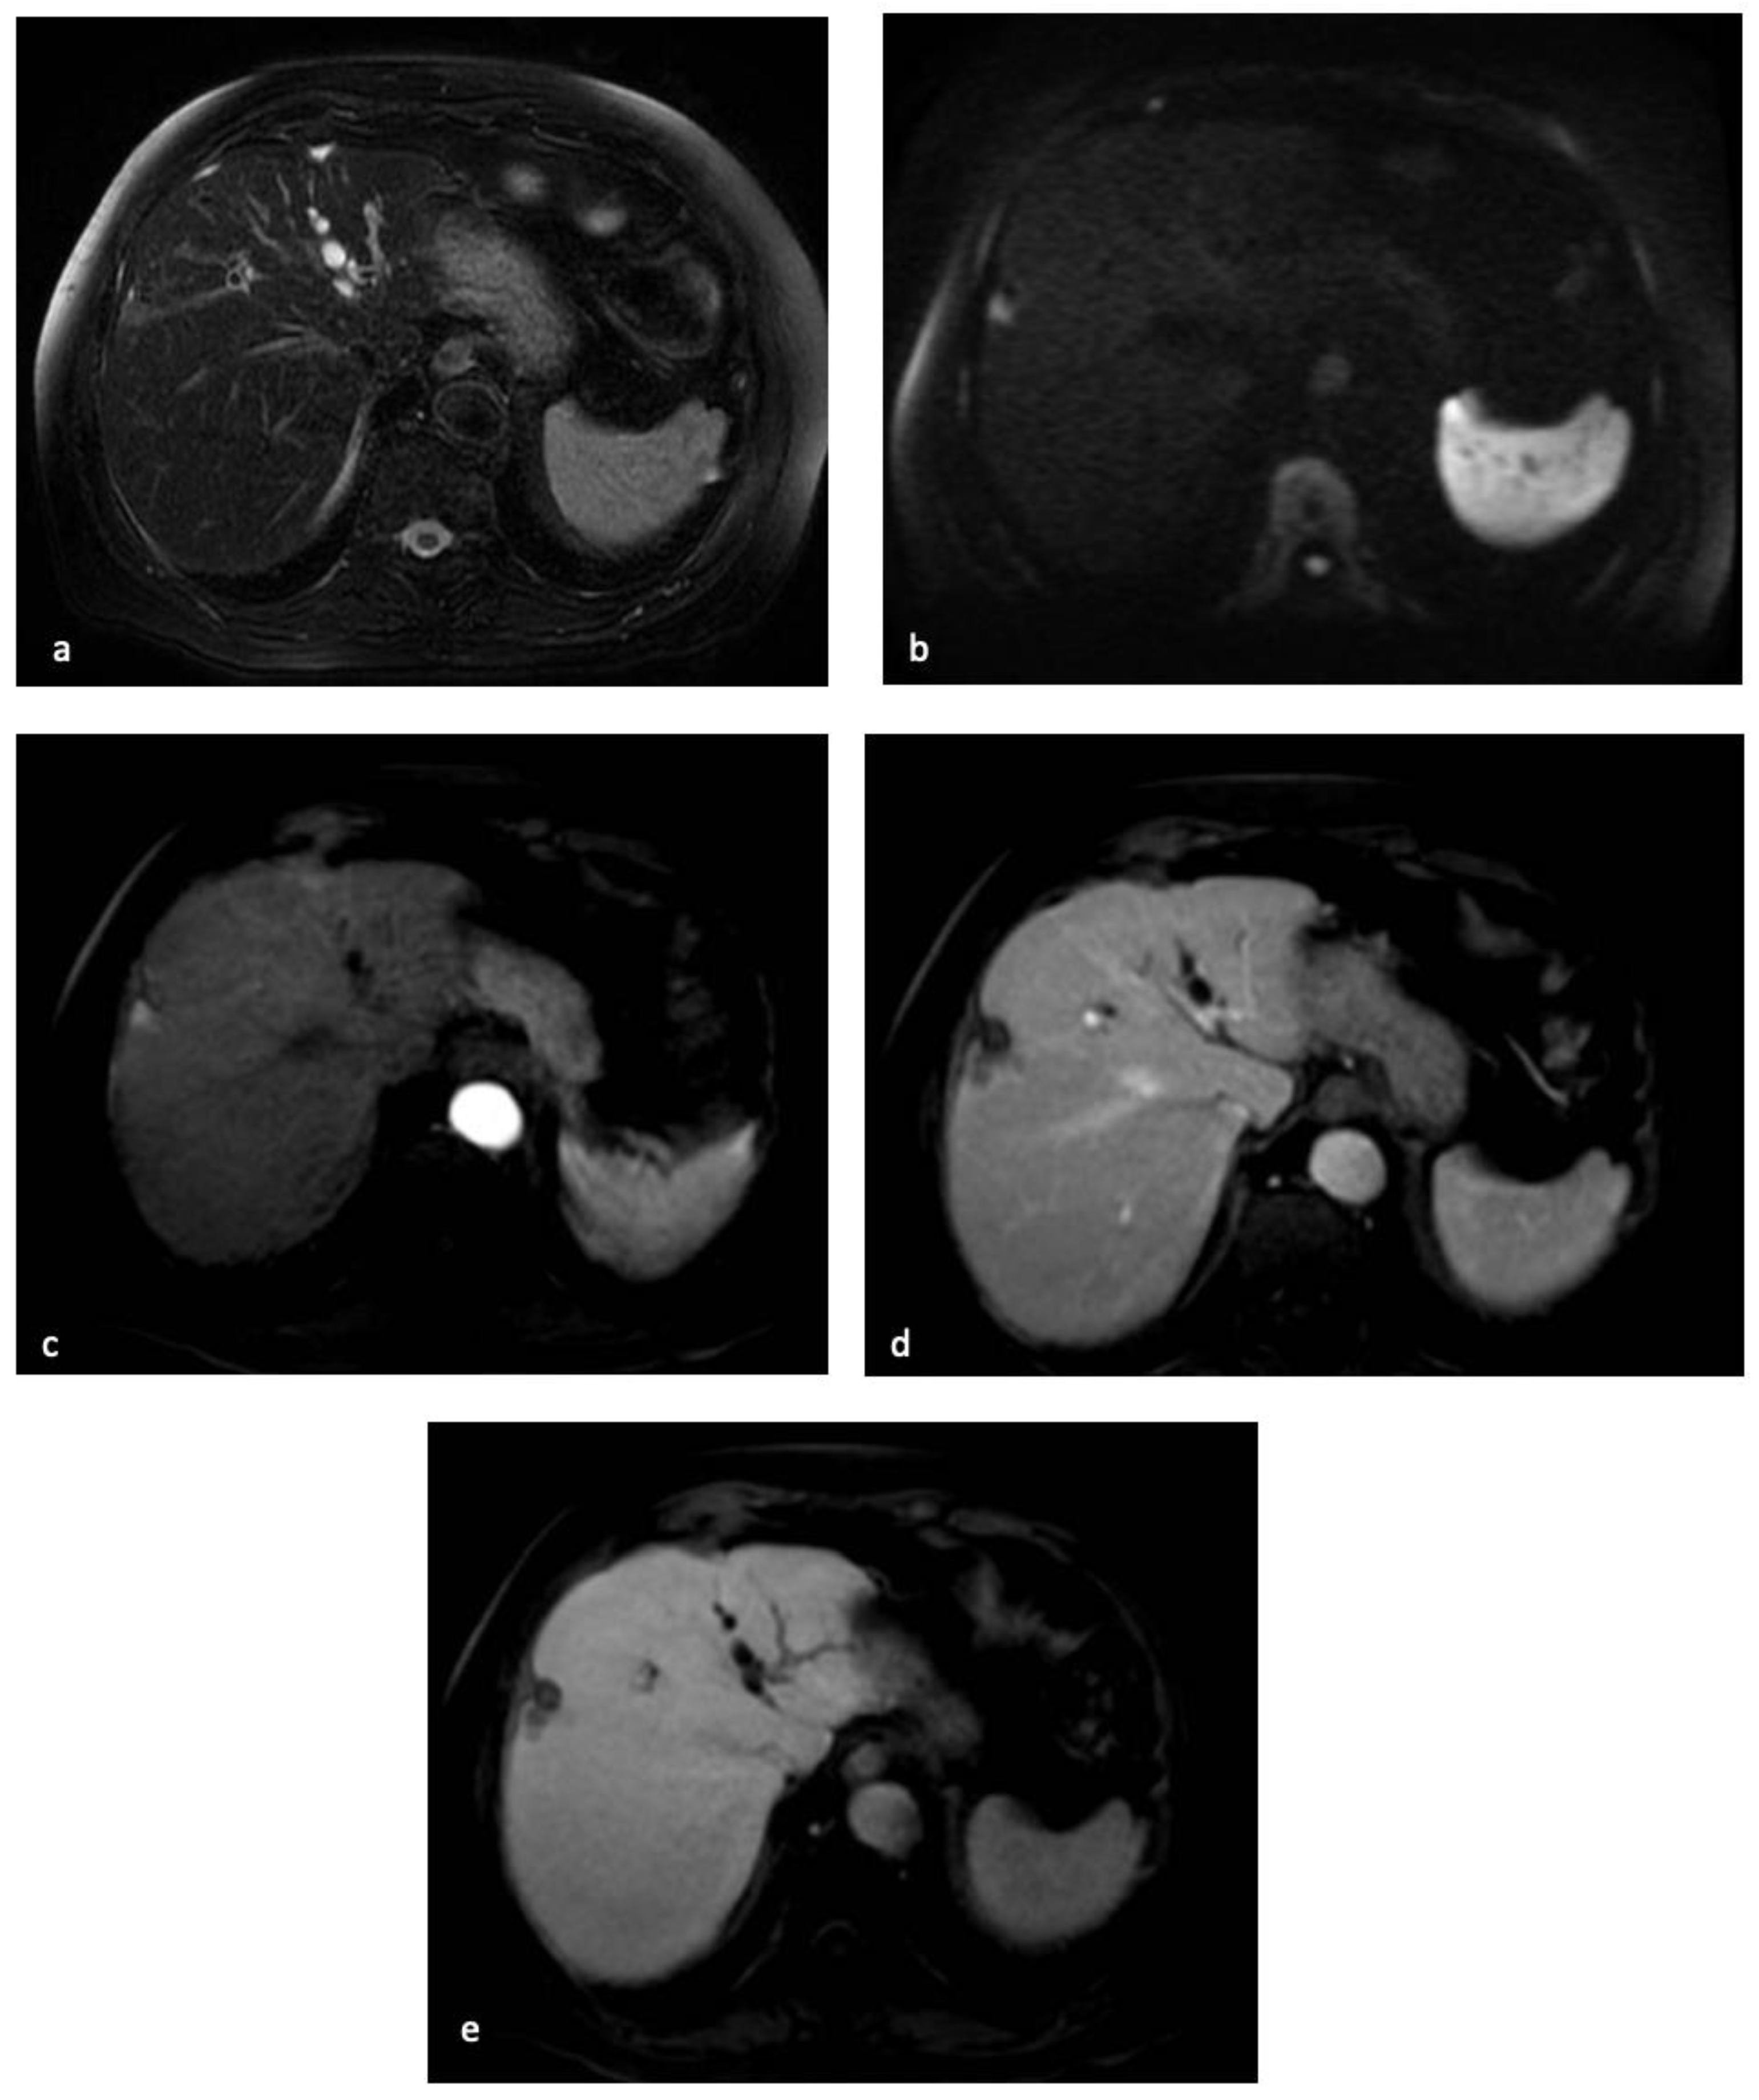

4. Magnetic Resonance Imaging

- Chan, M.V.; Huo, Y.R.; Trieu, N.; Mitchelle, A.; George, J.; He, E.; Lee, A.U.; Chang, J.; Yang, J. Noncontrast MRI for Hepatocellular Carcinoma Detection: A Systematic Review and Meta-analysis—A Potential Surveillance Tool? Clin. Gastroenterol. Hepatol. 2021, 20, 44–56.e2. [Google Scholar] [CrossRef]

- Zhao, C.; Dai, H.; Shao, J.; He, Q.; Su, W.; Wang, P.; Tang, Q.; Zeng, J.; Xu, S.; Zhao, J.; et al. Accuracy of Various Forms of Contrast-Enhanced MRI for Diagnosing Hepatocellular Carcinoma: A Systematic Review and Meta-Analysis. Front. Oncol. 2021, 11, 680691. [Google Scholar] [CrossRef]

- Semaan, S.; Violi, N.V.; Lewis, S.; Chatterji, M.; Song, C.; Besa, C.; Babb, J.S.; Fiel, M.I.; Schwartz, M.; Thung, S.; et al. Hepatocellular carcinoma detection in liver cirrhosis: Diagnostic performance of contrast-enhanced CT vs. MRI with extracellular contrast vs. gadoxetic acid. Eur. Radiol. 2019, 30, 1020–1030. [Google Scholar] [CrossRef]

- Shinmura, R.; Matsui, O.; Kobayashi, S.; Terayama, N.; Sanada, J.; Ueda, K.; Gabata, T.; Kadoya, M.; Miyayama, S. Cirrhotic Nodules: Association between MR Imaging Signal Intensity and Intranodular Blood Supply. Radiology 2005, 237, 512–519. [Google Scholar] [CrossRef]

- Cho, E.-S.; Choi, J.-Y. MRI Features of Hepatocellular Carcinoma Related to Biologic Behavior. Korean J. Radiol. 2015, 16, 449–464. [Google Scholar] [CrossRef] [PubMed]

- Granata, V.; Fusco, R.; Avallone, A.; Catalano, O.; Filice, F.; Leongito, M.; Palaia, R.; Izzo, F.; Petrillo, A. Major and ancillary magnetic resonance features of LI-RADS to assess HCC: An overview and update. Infect. Agents Cancer 2017, 12, 23. [Google Scholar] [CrossRef] [PubMed]

- Shankar, S.; Kalra, N.; Bhatia, A.; Srinivasan, R.; Singh, P.; Dhiman, R.K.; Khandelwal, N.; Chawla, Y. Role of Diffusion Weighted Imaging (DWI) for Hepatocellular Carcinoma (HCC) Detection and its Grading on 3T MRI: A Prospective Study. J. Clin. Exp. Hepatol. 2016, 6, 303–310. [Google Scholar] [CrossRef]

- De Gaetano, A.M.; Catalano, M.; Pompili, M.; Marini, M.G.; Rodríguez, C.P.; Gullì, C.; Infante, A.; Iezzi, R.; Ponziani, F.R.; Cerrito, L.; et al. Critical analysis of major and ancillary features of LI-RADS v2018 in the differentiation of small (≤2 cm) hepatocellular carcinoma from dysplastic nodules with gadobenate dimeglumine-enhanced magnetic resonance imaging. Eur. Rev. Med. Pharmacol. Sci. 2019, 23, 7786–7801. [Google Scholar]

- Park, M.J.; Kim, Y.K.; Lee, M.W.; Lee, W.J.; Kim, Y.-S.; Kim, S.H.; Choi, N.; Rhim, H. Small Hepatocellular Carcinomas: Improved Sensitivity by Combining Gadoxetic Acid–enhanced and Diffusion-weighted MR Imaging Patterns. Radiology 2012, 264, 761–770. [Google Scholar] [CrossRef] [PubMed]

- Kim, D.K.; An, C.; Chung, Y.E.; Choi, J.-Y.; Lim, J.S.; Park, M.-S.; Kim, M.-J. Hepatobiliary versus Extracellular MRI Contrast Agents in Hepatocellular Carcinoma Detection: Hepatobiliary Phase Features in Relation to Disease-free Survival. Radiology 2019, 293, 594–604. [Google Scholar] [CrossRef] [PubMed]

- Li, Y.; Chen, J.; Weng, S.; Yan, C.; Ye, R.; Zhu, Y.; Wen, L.; Cao, D.; Hong, J. Hepatobiliary phase hypointensity on gadobenate dimeglumine- enhanced magnetic resonance imaging may improve the diagnosis of hepatocellular carcinoma. Ann. Transl. Med. 2021, 9, 55. [Google Scholar] [CrossRef]

- Xiao, Y.-D.; Ma, C.; Liu, J.; Li, H.-B.; Zhang, Z.S.; Zhou, S.-K. Evaluation of hypointense liver lesions during hepatobiliary phase MR imaging in normal and cirrhotic livers: Is increasing flip angle reliable? Sci. Rep. 2016, 6, 18942. [Google Scholar] [CrossRef]

- Fujita, N.; Nishie, A.; Asayama, Y.; Ishigami, K.; Ushijima, Y.; Kakihara, D.; Nakayama, T.; Morita, K.; Ishimatsu, K.; Honda, H. Hyperintense Liver Masses at Hepatobiliary Phase Gadoxetic Acid–enhanced MRI: Imaging Appearances and Clinical Importance. Radiographics 2020, 40, 72–94. [Google Scholar] [CrossRef]